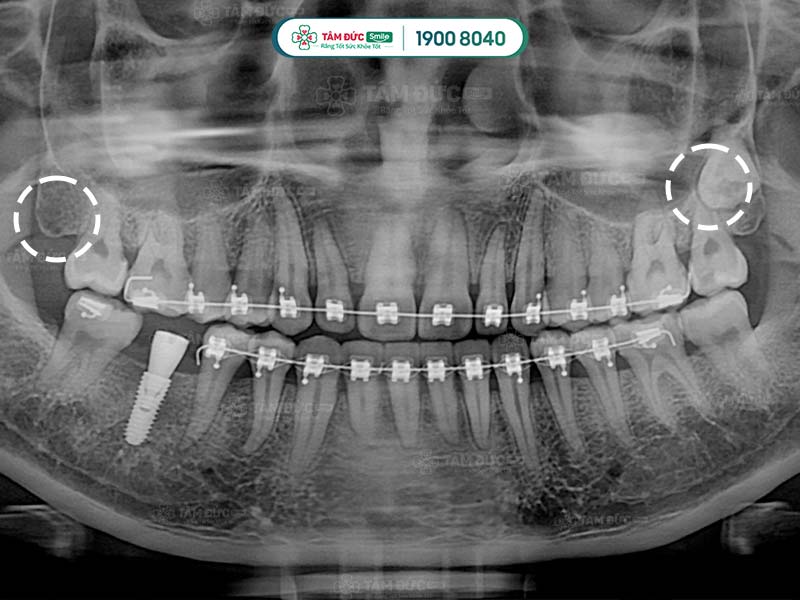

1.4. Bị viêm nướu răng có mủ do mọc răng khôn

Răng khôn là những chiếc răng mọc sau cùng, khi xương hàm và nướu đã phát triển ổn định. Không có đủ khoảng trống nên chúng thường sẽ mọc ngầm, mọc lệch hoặc xâm lấn với những chiếc răng khác trên hàm. Điều này có thể làm Quý khách cảm thấy đau nhức khó chịu và phải nhổ bỏ răng. Mặt khác, đau răng khôn còn ảnh hưởng tới sức khỏe răng miệng, trong số đó có bệnh lý viêm nướu răng có mủ.

Răng khôn mọc ngang làm chân răng kế cận bị tổn thương, gây ra viêm nướu có mủ

Điều trị viêm nướu răng có mủ tại Nha khoa Tâm Đức Smile